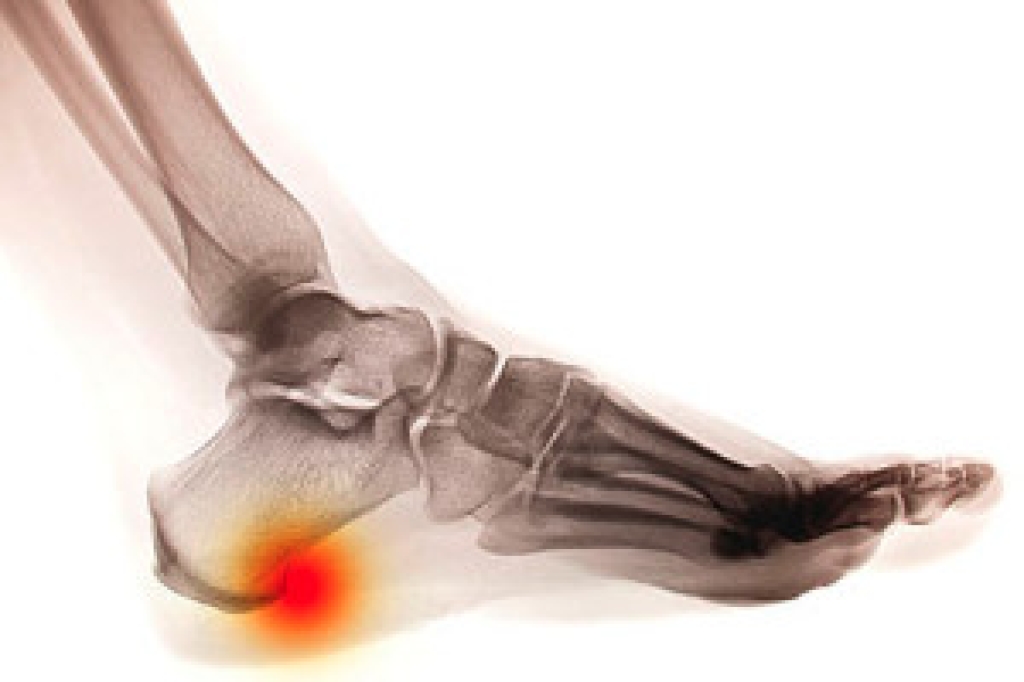

While it may not seem apparent with small ulcers on the foot, for diabetics, any size ulcer can become infected. Diabetics often also suffer from neuropathy, or nerve loss. This means they might not even feel when they have an ulcer on their foot. If the wound becomes severely infected, amputation may be necessary. Therefore, it is of the upmost importance to properly care for any and all foot wounds.

The best way to care for foot wounds is to prevent them. For diabetics, this means daily inspections of the feet for any signs of abnormalities or ulcers. It is also recommended to see a podiatrist several times a year for a foot inspection. If you do have an ulcer, run the wound under water to clear dirt from the wound; then apply antibiotic ointment to the wound and cover with a bandage. Bandages should be changed daily and keeping pressure off the wound is smart. It is advised to see a podiatrist, who can keep an eye on it.